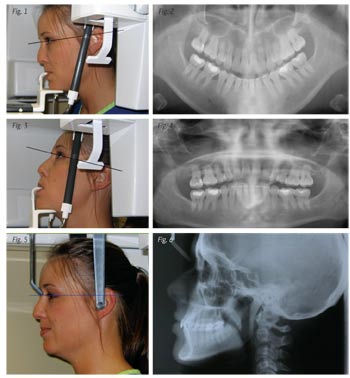

X-rays: Panex, Panorex: This Xray has great value to the orthodontist. It will show the development of the teeth, if there are congenitally absent teeth, supernumerary teeth, transposed teeth and the root relationship. The records tech must understand the patient positioning to achieve the best possible X-ray.

Improper positioning will result in the X-ray being distorted and teeth appearing elongated or shortened. When the head is positioned forward or down as in the photos, the teeth will appear shortened. Note the curve of the X-ray (Figs. 1 & 2).

If the head is positioned upward the teeth appear elongated (Figs. 3 & 4).

Cephalometric X-ray: This X-ray is traced to assist the orthodontist in determining the skeletal growth pattern and the jaw relationship. The level of the patient’s head is critical so that you don’t get a double image of the teeth or the mandible. In the event that the X-ray shows two mandible images and you are tracing the X-ray, split the difference and draw in the middle of the two images. It is also important to make sure the head is level to be able to clearly see the soft tissue. A patient’s profile can look different if his or her head is positioned up or down (Figs. 5 & 6).